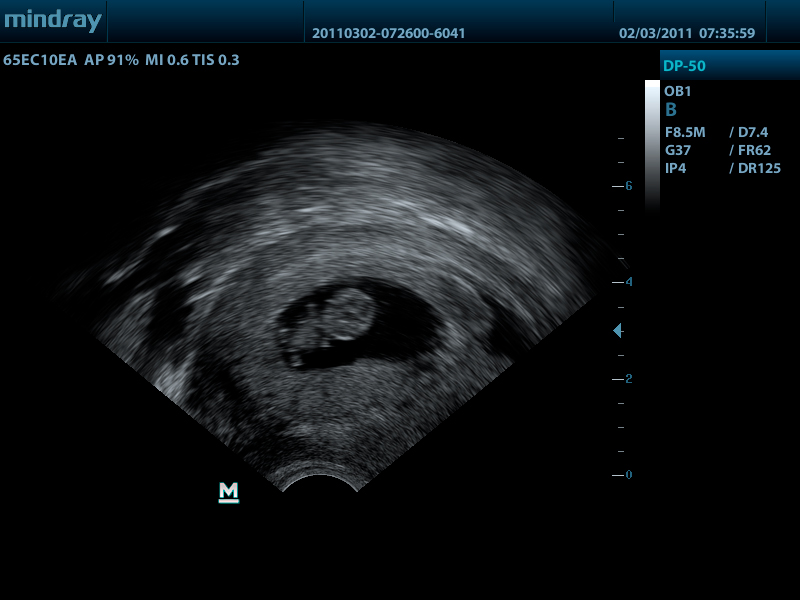

- Внутриполостной датчик 65EC10EA, 3.0 - 12.5 МГц, радиус кривизны 10 мм